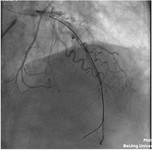

直接PCI冠脉导丝穿孔一例

冠脉导丝穿孔总结:1.重在预防:合理选择、使用和管理好导丝,尽早识别微小穿孔,结束前应有两个将心影完全包括在内的垂直体位造影;2.冠脉导丝引起的穿孔III型占很大一部分比重,预后更差;3.合理使用GPI,GPI可以放大无法分辨的冠脉穿孔;4.出现心包填塞,尽快心包穿刺,持续引流;5.冠脉穿孔应有心外科STAND BY。